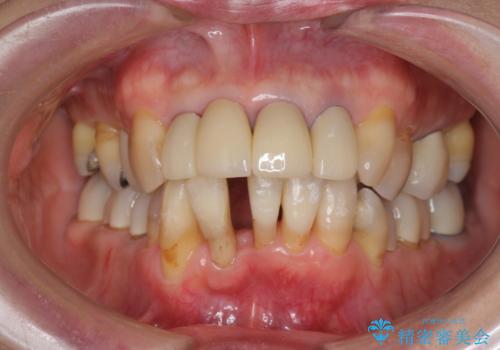

矯正を含む全顎治療

- 前歯の見た目・歯並び・銀歯の見た目の改善を求めて来院されました。

まずガタ付きの強い歯並びをマウスピース矯正インビザラインで整えたのち、セラミック治療による審美性の改善を計画します。